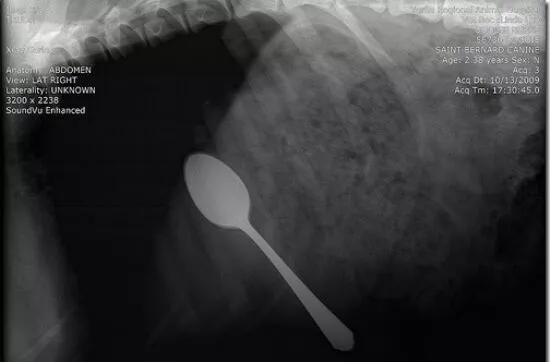

这是在狗狗胃里发现的勺子

这些都是在狗狗的胃里发现的,拍的X光图,看到那把刀在狗狗胃里,心里不紧张吗不担心 ,万一你家的狗狗也吃下去,想都不敢想!

狗狗似乎总是无法控制自己去吃一些没有营养价值的东西。针线、木勺、硬果壳、果核、塑料袋、珠宝、石块、抹布和袜子都有可能吃下去,狗狗胃内长期滞留这些异物不能被胃液消化,会造成胃黏膜损伤,影响胃功能。